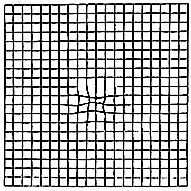

The Amsler Grid is a simple test to determine by the patient if there is a disturbance in the most vision sensitive area of the retina known as the macula. Swiss eye doctor Marc Amsler developed this grid in 1944 as he was studying the retina and doing pioneering work to map the field of vision. Amsler came to realize that any change in the macula tissue could be detected by the patient by viewing a grid on a chart. The test has the patient view a simple grid line chart, noting if there was any distortion of the grid lines or any waviness in the otherwise straight grid lines.

This chart has become the world standard in monitoring of the macula area. The grid is very much in wide use in eye doctors’ offices today.

The Amsler grid. Click here to go to the instruction

page and a printable version of the Amsler grid.

The Amsler grid as seen by the patient if there is a disturbance in the macula tissue.